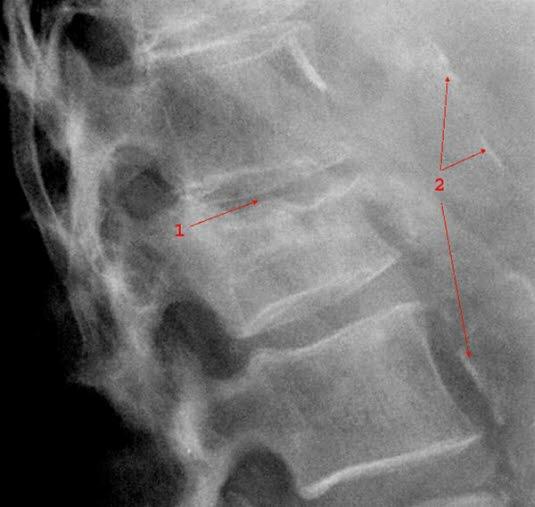

Ulike bruddtyper

Ulike bruddtyper kan oppstå:

- Kompresjonsbrudd

- Betyr at selve virvelen er blitt presset sammen i lengderetningen (se illustrasjonene over). En bruddtype som er vanlig ved beinskjørhet, og som vanligvis er et stabilt brudd.

Røntgen kan avklare diagnosen. Ved mistanke om instabilitet og ved nakkeskader tas CT. MR tas kun ved behov for bedre bilder av ryggmargen og leddbånd.